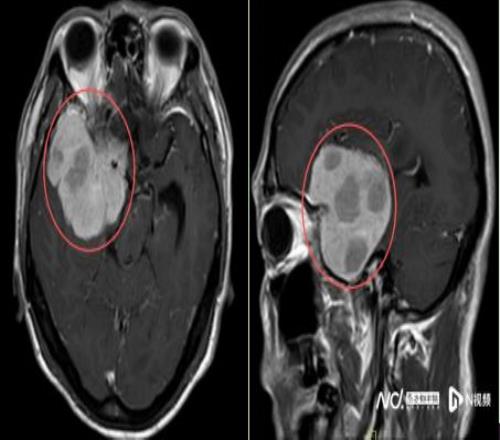

鉴于肿瘤体积巨大、位置较深,考虑为右侧额颞蝶骨嵴内侧型巨大脑膜瘤,肿瘤突入垂体窝和斜坡,环绕颈内动脉及分支、视神经等重要结构,压迫脑干。手术难度是神经外科最复杂的手术之一,犹如刀尖上行走,且已出现进行性神经功能缺损症状:肢体乏力,视力受损,视物重影等,病情复杂、手术风险极高。

手术在高倍显微镜下进行,由彭彪主任主刀。他带领团队凭借丰富的临床经验和精湛技术,精准判断肿瘤边界,操作如“绣花”般细致,一分一毫谨慎分离,既避免了损伤视神经导致视力丧失,又保护了颈内动脉及其分支,在控制出血的同时确保大脑整体血供稳定。

经过近8个小时的精细操作,肿瘤被完整切除,重要神经血管结构完好保留。术后患者恢复良好,顺利出院,经过积极康复后,陈叔有望重回马拉松赛场。